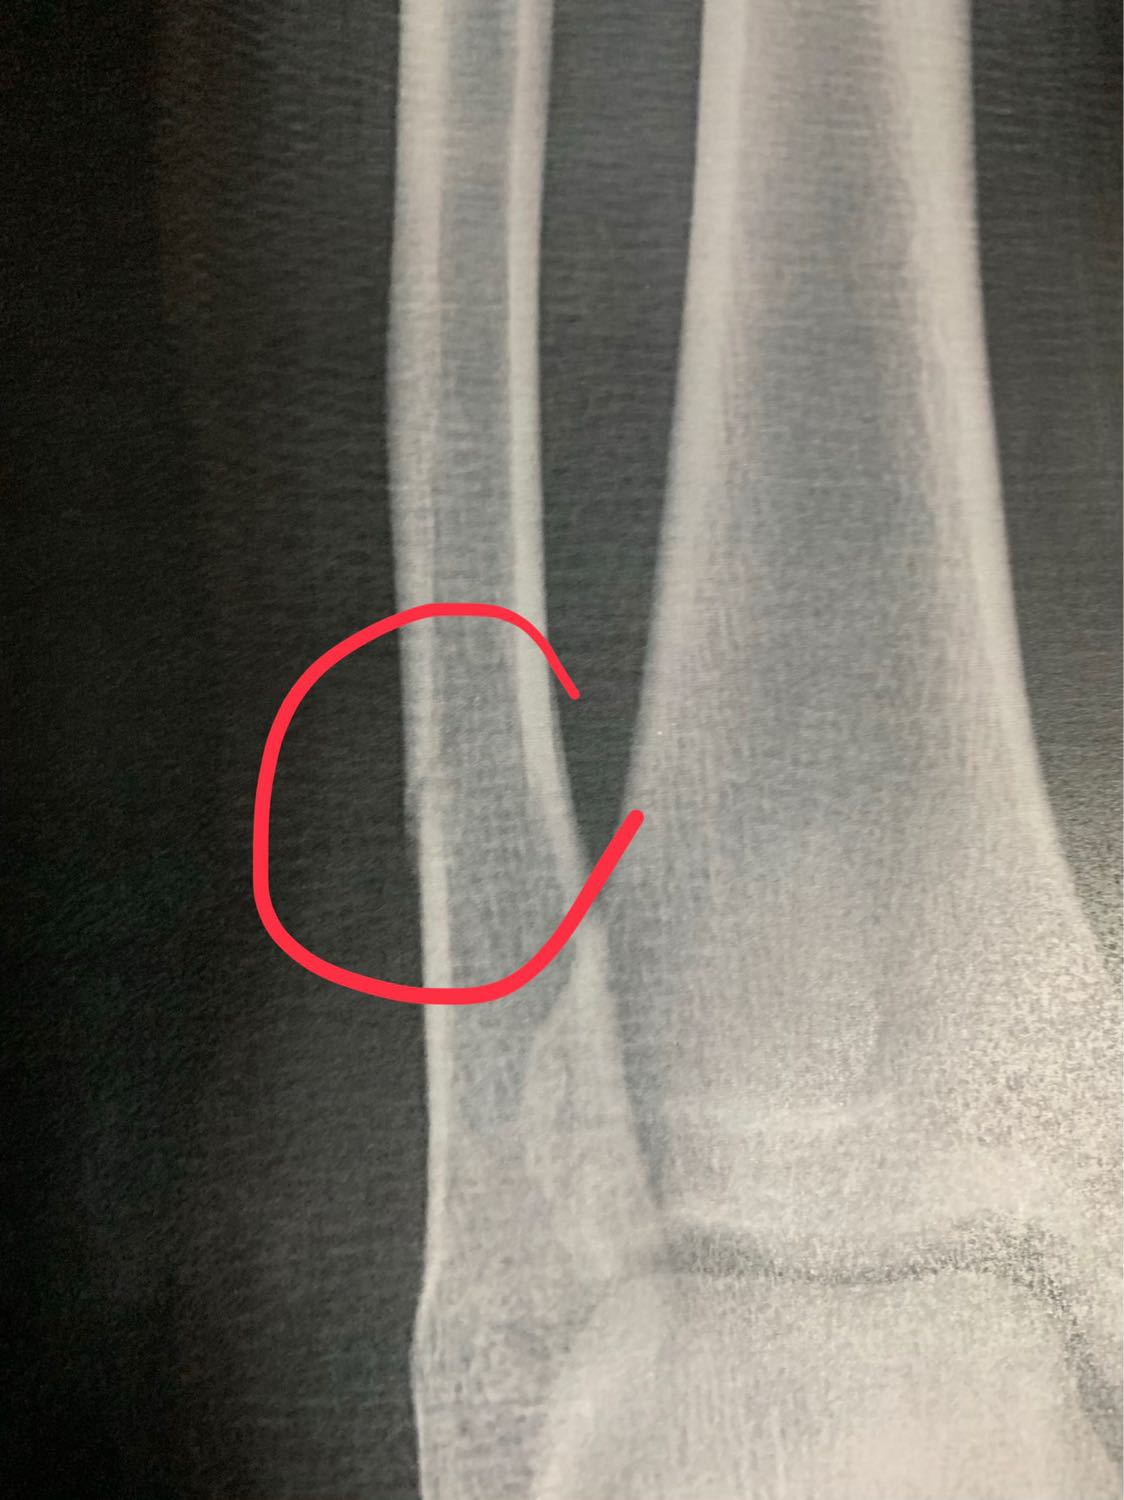

น้องอายุ16 กระดูกร้าว ควรต้องผ่าตัดไหมครับ

ตามภาพข้างบนเลยครับ คือไปหาหมอมาหลายหมอ มีทั้งแนะนำให้ผ่า และไม่ต้องผ่า แต่ส่วนตัวคือไม่อยากให้น้องผ่า เพราะคิดว่าน้องชายอายุยังน้อย กระดูกน่าจะเชื่อมต่อกันเร็ว เลยไม่อยากให้ผ่า เลยอยากรบกวนสอบถามผู้มีความรู้ หรือประสบการณ์หน่อยครับ จะได้ตัดสินใจว่าจะทำไงต่อไป พ่อแม่ก็2จิต2ใจครับ

ปล. กระดูกตรงน่องครับ